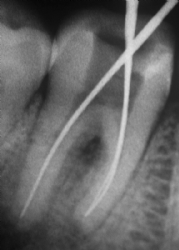

Beherdungen um die Wurzelspitze mit Schwellung und Schmerzen können folgen. Um so einen Zahn zu erhalten, muss das Gewebe aus den Hohlräumen (Wurzelkanäle, Zahnmarkhöhle) entfernt werden, von allen Verunreinigungen (Bakterien!) gesäubert werden und dann dicht verschlossen werden.

Wurzelbehandelte Zähne erfüllen oft noch jahrzehntelang ihre Aufgaben und sind meist nur im Röntgenbild von anderen zu unterscheiden.